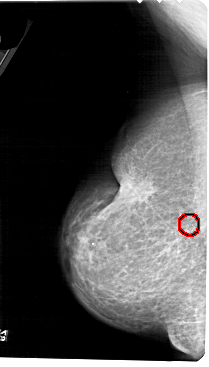

A_1655_1.LEFT_MLO

LEFT_MLO LINES 5491 PIXELS_PER_LINE 3121 BITS_PER_PIXEL 12 RESOLUTION 43.5 OVERLAY

FILE: A_1655_1.LEFT_MLO.OVERLAY

TOTAL_ABNORMALITIES 1

ABNORMALITY 1

LESION_TYPE CALCIFICATION TYPE PLEOMORPHIC DISTRIBUTION CLUSTERED

ASSESSMENT 4

SUBTLETY 5

PATHOLOGY BENIGN

TOTAL_OUTLINES 1